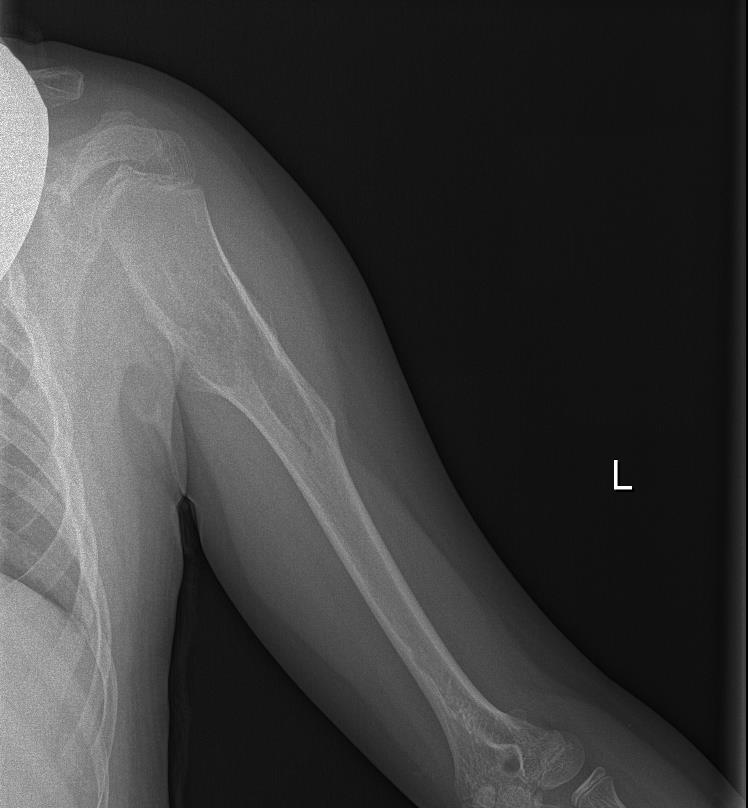

Radiografía de Miembro superior izquierdo: Se visualiza lesión lítica metafiso-diafisaria en húmero izquierdo expansiva con excrecencias óseas y margen estrecho con hueso sano.